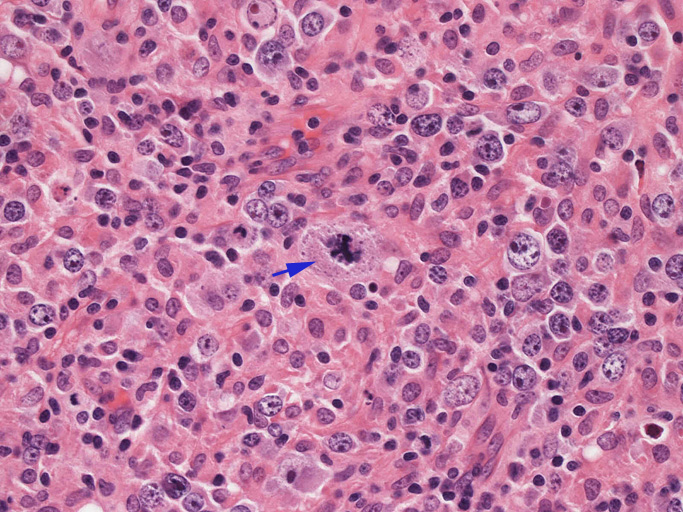

結節構造内では, 好酸性細胞質をもつ組織球の増生を背景に大型異型細胞が散在性または集蔟して増殖している。被膜下にも線維化組織内にbizzarreな大型細胞が認められる。リンパ球は小型リンパ球が大型異型細胞を含む組織球性の結節辺縁に存在する。大型細胞は, centroblastic cellが多く, その他 Hodgkin cell-like cell, RS細胞様巨細胞, 腎臓型の核をもった細胞, 多型核の細胞など多彩な形態を示す。異型核分裂像をふくむ核分裂像が多い。

大型異型細胞の形態

腫瘍細胞はCD20+, CD30+, CD15-, PAX-5+, Oct.2+, BOB.1+(Oct2, BOB1は田丸先生の染色結果), EBER-ISH+, EBNA2-